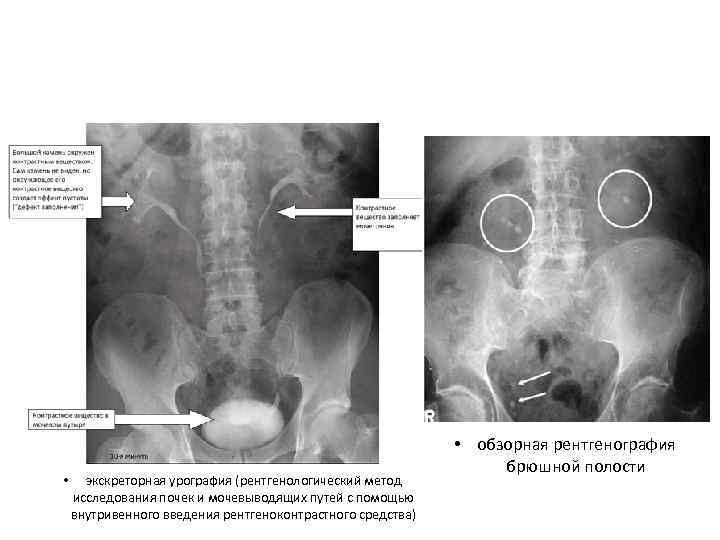

Диагностика • Анализ анамнеза заболевания и жалоб. • Анализ анамнеза жизни. • Данные врачебного осмотра (положительный симптом поколачивания — боль при легких ударах в поясничной области). • Анализ крови — сдвиг лейкоцитарной формулы влево, повышение СОЭ (скорость оседания эритроцитов, неспецифический признак воспаления). • Анализ мочи — появляются эритроциты, единичные цилиндры (своего рода слепки канальцев почек, которые состоят из свернувшихся в кислой среде мочи белков и других компонентов, важный признак почечной патологии) и соли, лейкоцитурия (обнаружение лейкоцитов в моче — признак воспаления) Эндоскопические методы: • Цистоскопия • УЗИ Рентгенологические методы: • обзорная рентгенография брюшной полости • экскреторная урография • Динамическая сцинтиграфия • Компьютерная томография с контрастированием

• экскреторная урография (рентгенологический метод исследования почек и мочевыводящих путей с помощью внутривенного введения рентгеноконтрастного средства) • обзорная рентгенография брюшной полости